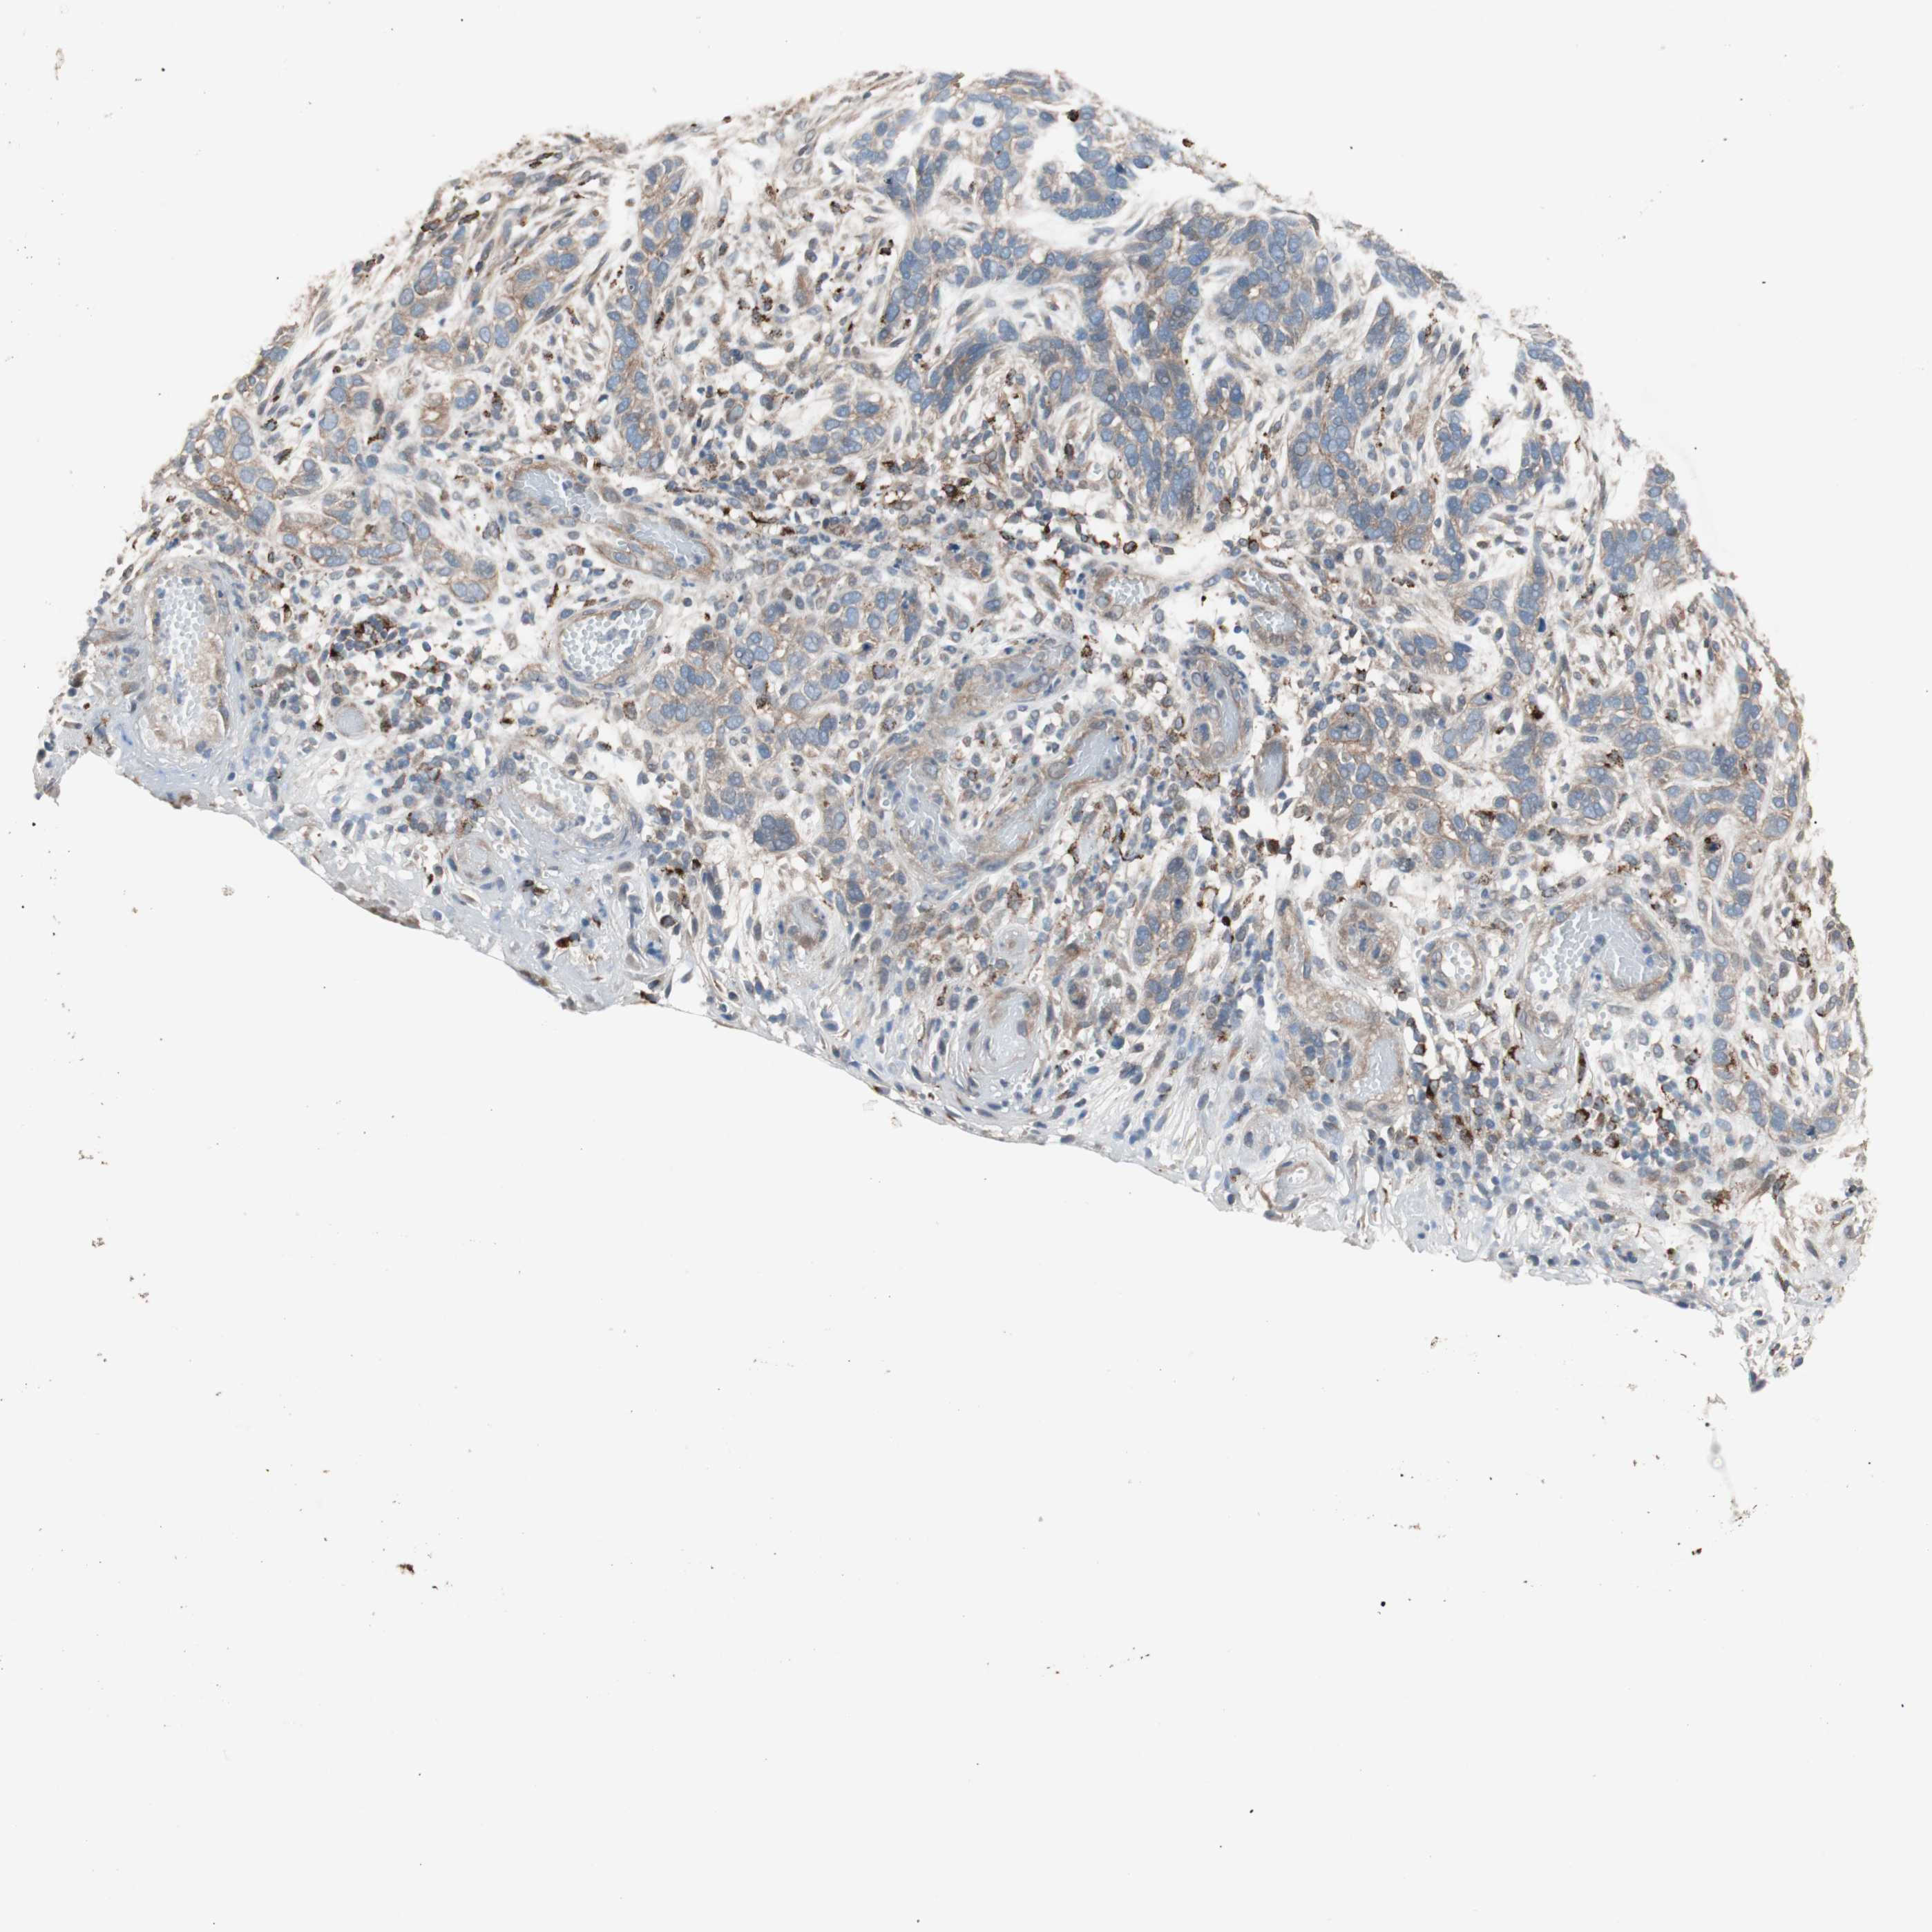

SKIN CANCER - Protein expressioni

A mouse-over function shows sample information and annotation data. Click on an image to view it in a full screen mode. Samples can be filtered based on level of antibody staining by selecting one or several of the following categories: high, medium, low and not detected. The assay and annotation is described here.

Antibody stainingi

Antibody staining in the annotated cell types in the current human tissue is reported as not detected, low, medium, or high, based on conventional immunohistochemistry profiling in selected tissues. This score is based on the combination of the staining intensity and fraction of stained cells.

Each image is clickable and will lead to virtual microscopy that enables deeper exploration of all samples and also displays staining intensity scores, fraction scores and subcellular localization as well as patient and tissue information for each sample.

Antibody HPA006543

Staining

High

Intensity

Strong

Quantity

>75%

Location

Nuclear

Squamous cell carcinoma, NOS